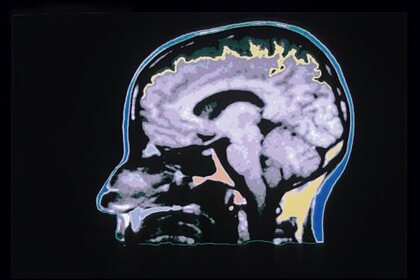

Британские ученые обнаружили указывающие на признаки рака «горячие точки» в мозгу. Результаты исследования опубликованы в журнале Neuro-Oncology Advances, передает РИА Новости.

Специалисты выяснили, что есть специфичные скопления клеток вокруг кровеносных сосудов, которые определяют места, где опухоли могут быть злокачественными. По их мнению, именно эти участки могут являться рассадниками злокачественного прогрессирования, то есть процесса из-за которого опухоль быстро и неконтролируемо разрастается. Отмечается, что данное исследование имеет огромное значение, так как оно позволит с большей вероятностью определять, когда опухоль головного мозга становится злокачественной.